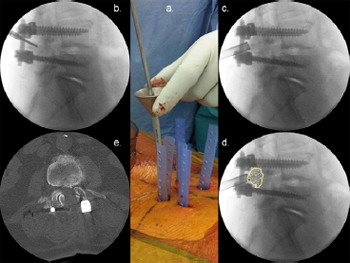

5.3.1. Illustrative patient 3

A 69-year-old male presented with progressive paraparesis and

cord compression at T9. He had metastatic lung cancer with an expected

longevity of less than 12 months. MIS decompression was

proposed; however, stabilisation was recommended due to the

anterior compression and pediculectomy/partial vertebrectomy

necessary for adequate tumour resection. Surgical time was 2

hours and 35 minutes with 210 mL of blood loss and a length of stay (LOS) of 5 days. The patient remained independently mobile

until his death 7 months following surgery.

Fig. 12. Illustrative patient 2, a 69-year-old male who presented with progressive

paraparesis and cord compression at T9. (a) Sagittal T2-weighted MRI showing T9

cord compression from lung metastasis (arrow); (b) intra-operative photograph

showing percutaneous screw fixation; (c) sagittal post-operative CT scan reconstruction

showing partial vertebrectomy and decompression; and (d) post-operative

three-dimensional CT scan reconstruction showing stabilisation.